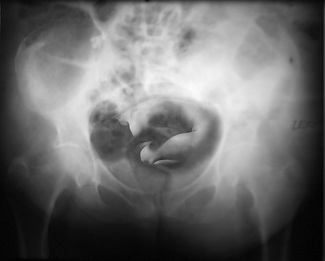

Ken Weissblum USA Nominee "the Beginning" These images are part of a series called Roentgen's Dreams which blend two apparently contradictory, yet traditional imaging techniques used with the human body: reflective photography and penetrative |

Perry Mears UK Nominee "embryo " Tillie, ever sensitive to the setting |